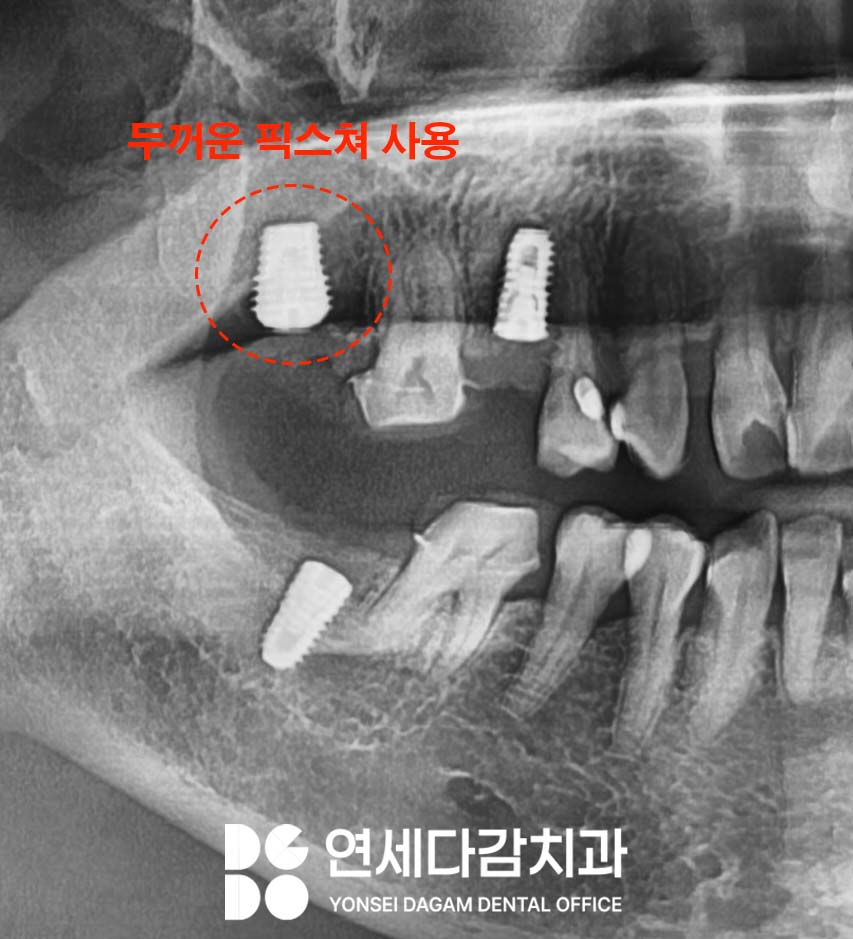

그러나 가락동 치과 에서 앞서

히스토리 설명드린 것처럼

이미 두꺼운 고정체로도

실패한 히스토리가 있었기 때문에,

다른 접근 방식이 필요했습니다.

골밀도가 전반적으로 낮다는

점을 고려하여,

상악동 저부에 위치한 피질골을

적극 활용하는 전략을 수립했습니다.

피질골은 뼈의 외측에 위치하여

단단하고 치밀한 뼈조직으로,

해면골에 비해

우수한 고정력을 제공할 수 있습니다.

이와 동시에 일반적으로 사용되는

길이보다 더 긴 고정체를 선택하여,

근단부(끝부분)가 상악동 저의

피질골에 닿도록 시행했습니다.

이를 통해 상악동 저의

단단한 피질골에서 고정력을

얻을 수 있었습니다.